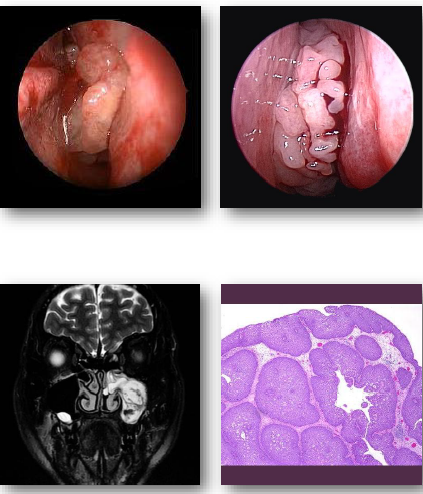

sinonasal papillomas overview

Benign epithelial tumors of sinonasal mucosa

•Includes inverted and exophytic variants

•Associated with HPV infection in some cases

•Locally aggressive with recurrence potential

•Small risk of malignant transformation exists

sinonasal papillomas clinical features

•Unilateral nasal obstruction or visible mass

•May present with epistaxis or discharge

•Often arises from lateral nasal wall

•May extend into adjacent sinus spaces

•Symptoms depend on size and location

sinonasal papillomas management and prognosis

•Surgical excision required for treatment

Complete removal reduces recurrence risk

•Long-term follow-up recommended

•Recurrence relatively common

•Small risk of malignant transformation

fungiform sinonasal papilloma

inverted sinonasal papilloma